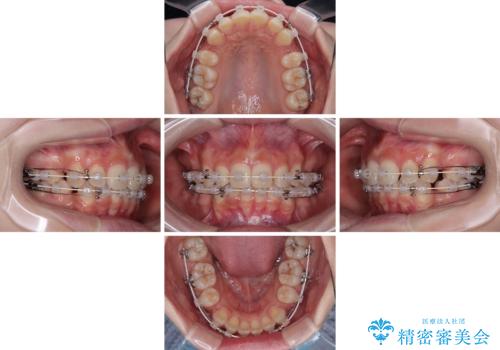

- 矯正装置

- 審美装置

- 治療期間

- 2年11ヶ月

- 治療回数

- 30回以上